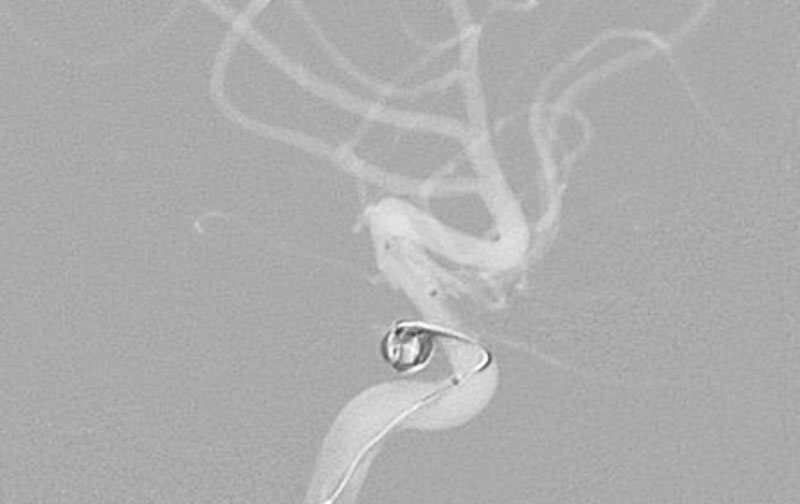

No.1631 手術前